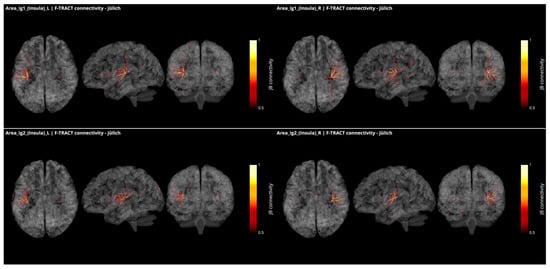

In Figure 4, all connections from the granular subregions Ig1 and Ig2 of the insula, which present borders with both the parietal operculum and the temporal cortex, are displayed with the same methodology and threshold as for Figure 3. These regions show strong connections with one another and with Ig3, as well as with dysgranular parts of the insula. They also present connections with the subregions of the OpP and with the subregions of the Heschl gyrus and the superior temporal gyrus. Additional connection was found with the motor area 4p and frontal area 44 from right Ig1. All but left Ig2 were connecting to the inferior parietal lobule.

Figure 4.

Intracortical connectivity of the two granular subregions of the insula. From top to bottom: area Ig1 and area Ig2. Left column for the subregions of the left hemisphere and right column for the subregions of the right hemisphere. Image derived from the data of the F-TRACT project (https://f-tract.eu), version of 1 December 2021.

The richness of the connections between OpP and the insula, the auditory and the somatosensory areas confirms that OpP can be considered as a multimodal region, potentially involved in sensory and auditory integration. However, since electrodes were not covering all cortical regions, additional connectivity pathways could remain unobserved.